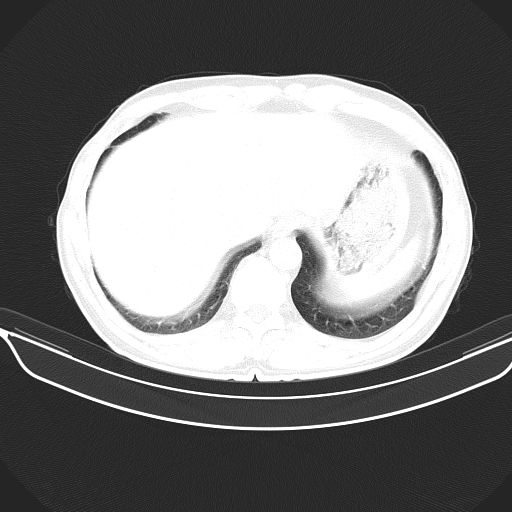

以下是引用shuiyuan在2010-3-1 10:45:00的发言:[br]考虑左肺上叶中心型肺癌伴阻塞型炎症,邻近胸膜受侵。

以下是引用心路寻觅在2010-3-1 10:23:00的发言:[br]1、考虑左肺上叶周围型肺癌[br]2、右上肺陈旧性病灶。[br][br][本贴已被 心路寻觅 于 2010-3-1 10:40:18 修改过]